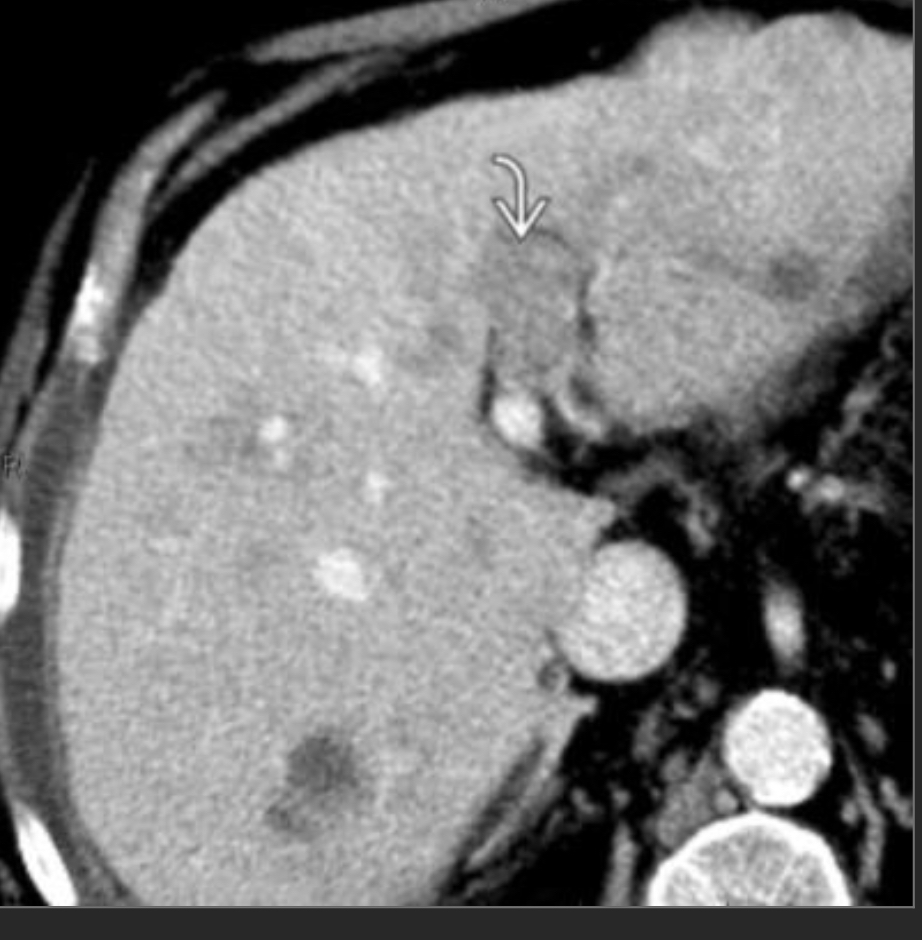

Incidentally seen liver lesion.

Isodense to liver on other phases

FNH

homogeneously hypervascular on arterial phase imaging and nearly isodense to liver on other phases; the additional presence of a central scar is essentially pathognomonic.

—> in a younger woman w/o hx of cancer, can be dx from the CT appearance

—>hemangioma would be hypervascular but isodense to vessels, not liver.